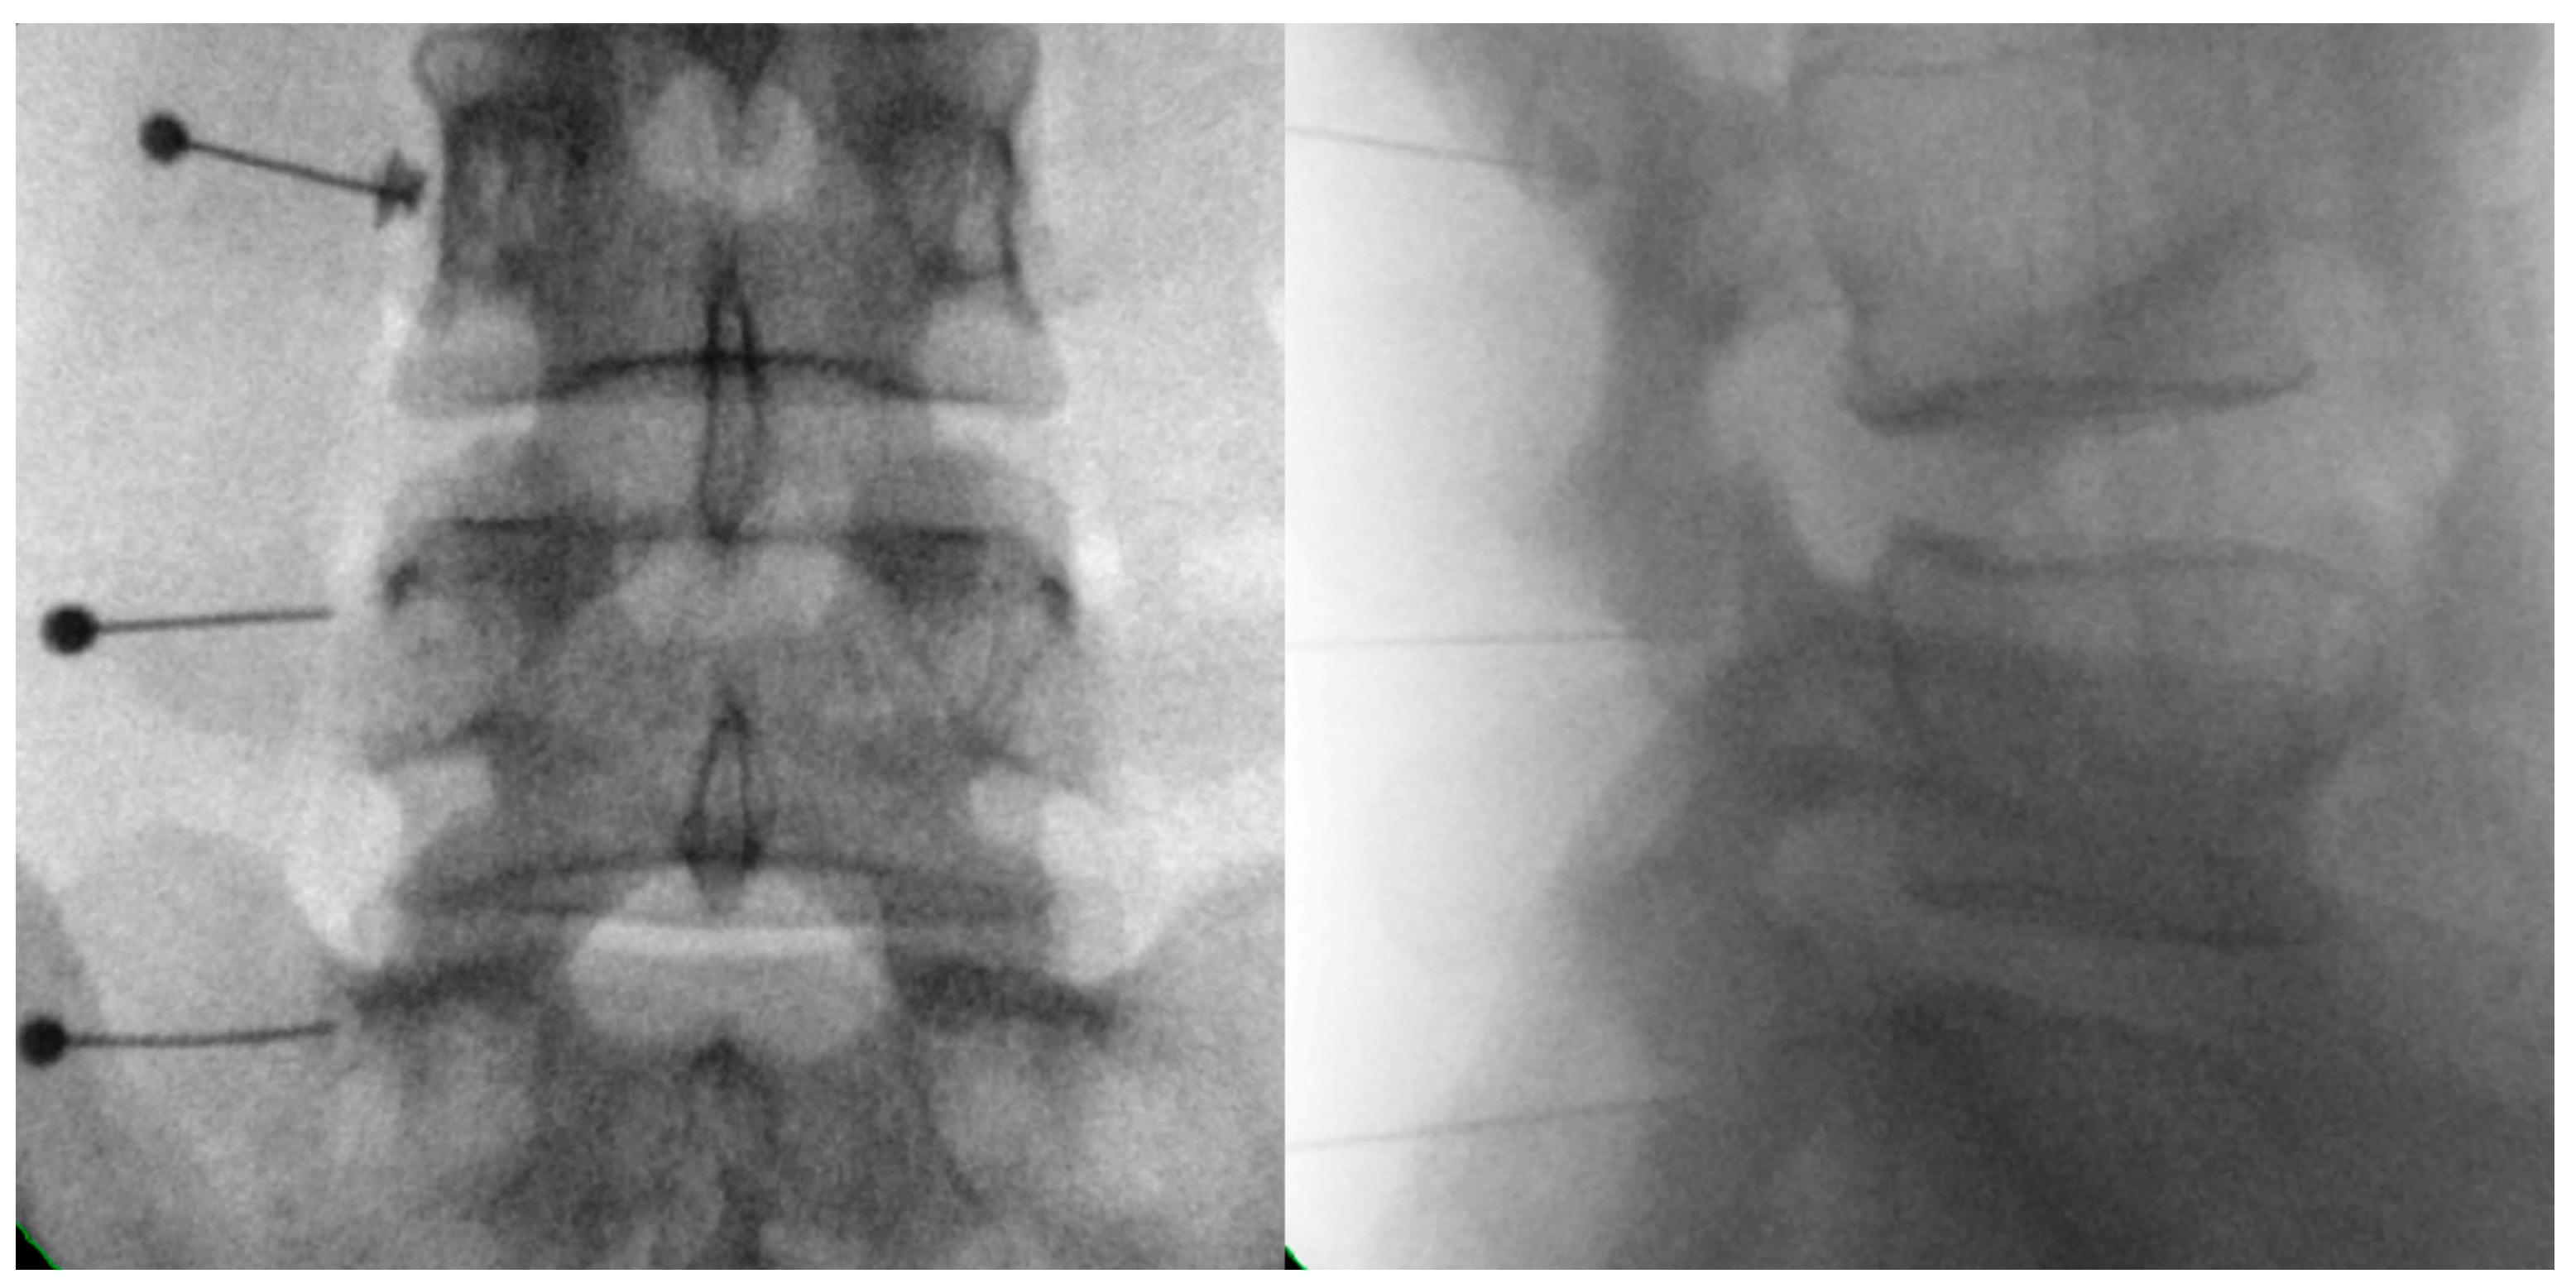

- Park, S.H.; Ji, G.Y.; Cho, P.G.; Shin, D.A.; Yoon, Y.S.; Kim, K.N.; Oh, C.H. Clinical Significance of Epidurography Contrast Patterns after Adhesiolysis during Lumbar Percutaneous Epidural Neuroplasty. Pain. Res. Manag. 2018, 2018, 6268045. [Google Scholar] [CrossRef] [PubMed]